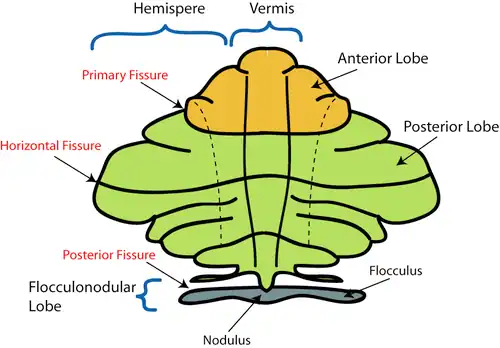

Schematic representation of the major anatomical subdivisions of the cerebellum. Superior view of an "unrolled" cerebellum, placing the vermis in one plane. | |

The cerebellum consists of three parts, a median and two lateral, which are continuous with each other, and are substantially the same in structure. The median portion is constricted, and is called the vermis, from its annulated appearance which it owes to the transverse ridges and furrows upon it; the lateral expanded portions are named the hemispheres.

- The "intermediate hemisphere" is also known as the "spinocerebellum".

- The "lateral hemisphere" is also known as the "pontocerebellum".

- The lateral hemisphere is considered the portion of the cerebellum to develop most recently.[1]